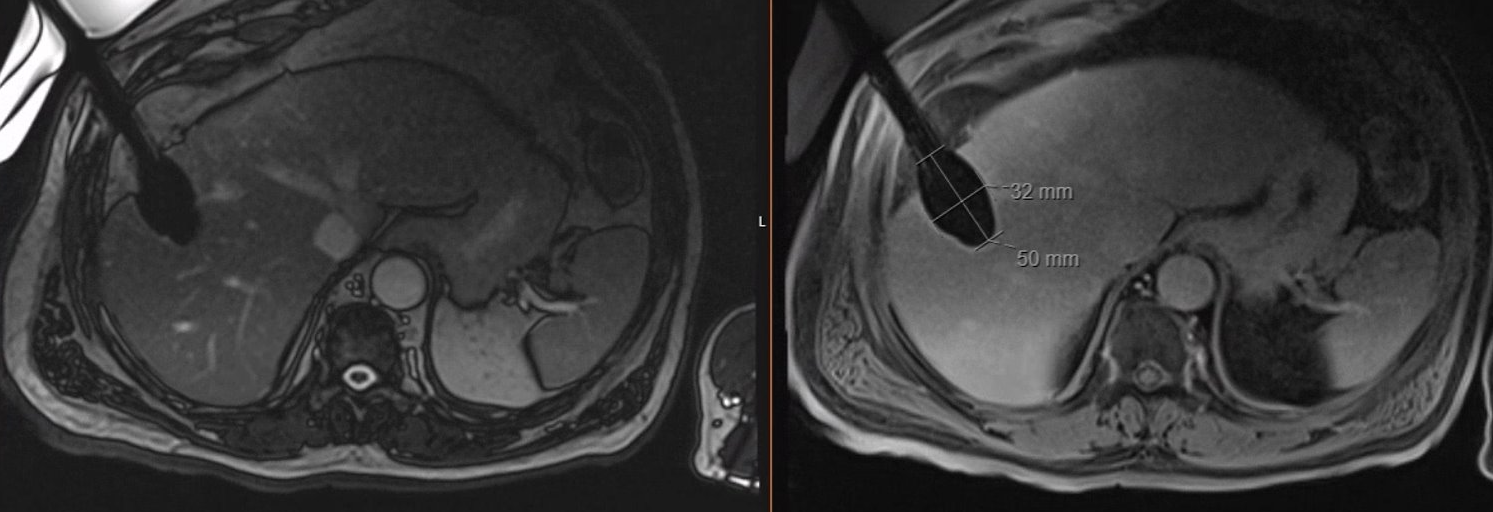

A small hepatocellular carcinoma is shown on MRI. It demonstrates arterial enhancement after gadolinium injection.

The same lesion is visible on non-contrast MRI (Trufi), ensuring easy targeting with MRI guidance.

Real-time MRI guidance is used to place the first cryoprobe into the lesion.

The ice ball is well visualised on all MRI sequences, ensuring complete coverage of the tumour with margins to spare.